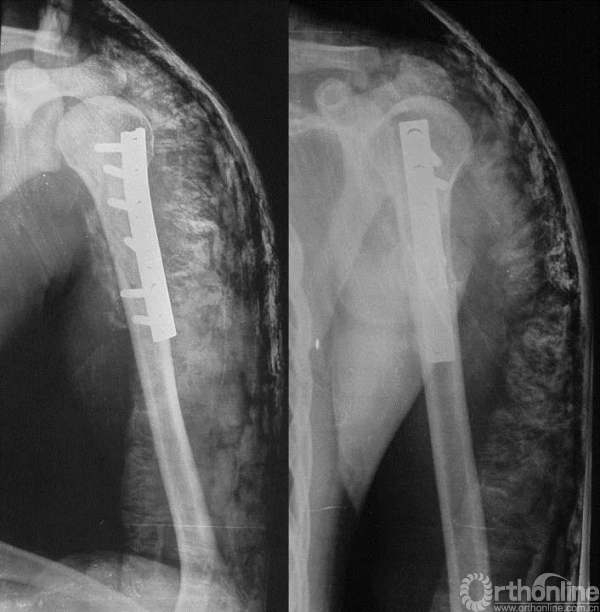

图13-5 病例一术后X线平片正侧位

术后病理报告示“倾向于侵袭性骨母细胞瘤”。

患者术后4个月发现原手术切口出现包块。

于当地医院未行病理学检查,直接手术行“病灶刮除、钢板内固定术”。